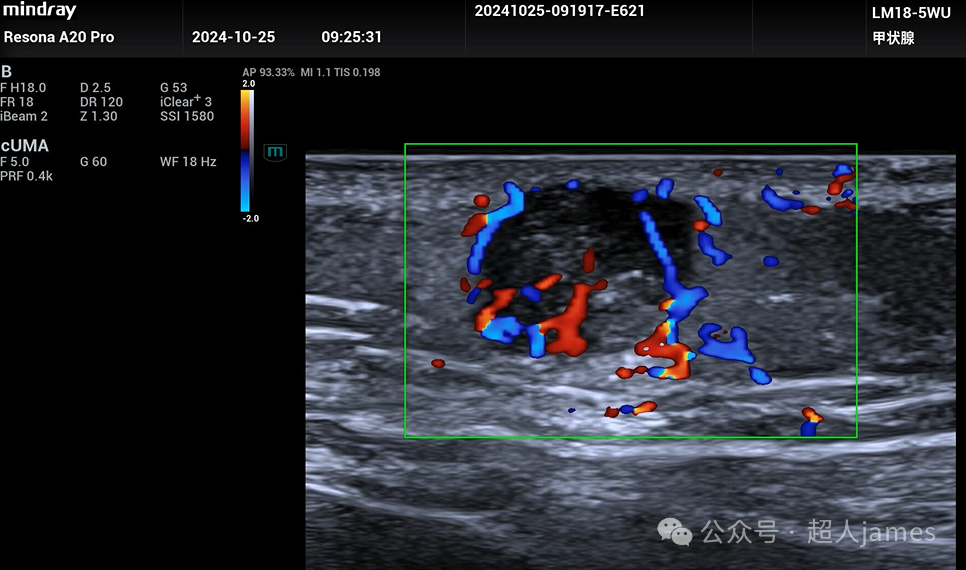

超声表现多样,可以表现为实质片状钙化型、点状钙化灶型、无钙化型、完全钙化型等,边界清晰,后方衰减。利用UMA超微血流成像显示:实质区域可以探及血流信号,这一点是与皮脂腺囊肿、表皮样囊肿的重要鉴别点。